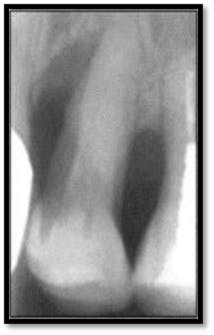

Initial perio charting (above left), Pretreatment radiograph (above right)

As you can see, the extent of bone loss on the mesial is significant, almost to the apex.14 months post treatment: